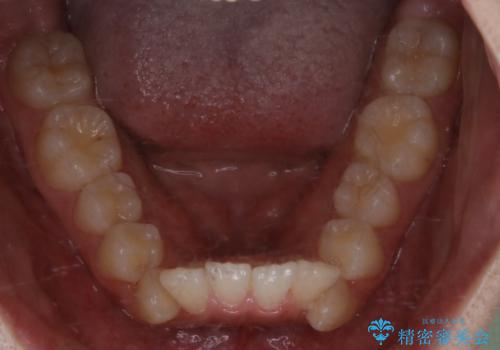

- 出っ歯が気になるとご相談にいらした方です。抜歯して歯を並べました。深かった噛み合わせも改善させることが出来ました。

噛み合わせが元々深い方は一般的に噛む力が強く、治療に時間がかかる傾向にあります。治療前の想定よりも短期間でスムーズに治療を終える事ができ、大変喜んでいただけました。リテーナーによる保定もしっかり行っていただいており、後戻りなく快適にすごして頂けているとのことです。